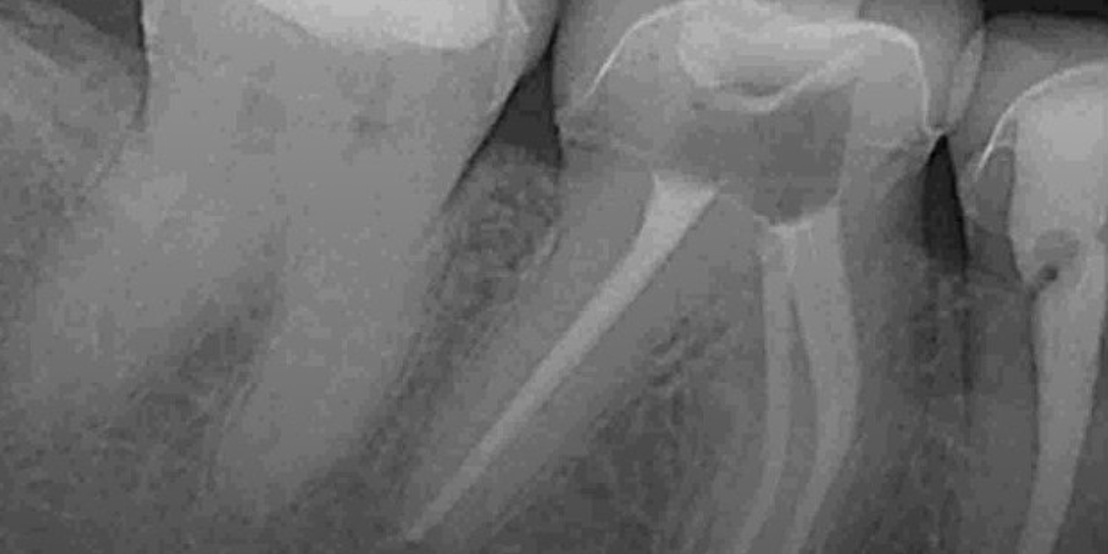

Root canal therapy removes infected pulp while preserving the natural tooth, offering pain relief and preventing further issues. At our clinic, we perform root canal Dubai procedures using advanced tools for accurate cleaning and long-term results.

In cases of severe pain, we offer emergency root canal Dubai services to treat infections promptly. Our team follows proven root canal treatment steps in Dubai to ensure your comfort and a smooth recovery. A crown is placed afterward to restore function and protect your natural smile.

Our modern root canal Dubai is designed to relieve discomfort while preserving your natural tooth. Using advanced technology and a gentle root canal treatment steps Dubai, we effectively remove infection and seal the area to ensure long-term strength and protection. This treatment restores function and comfort with minimal downtime, helping you maintain a healthy, confident smile. +97145641222